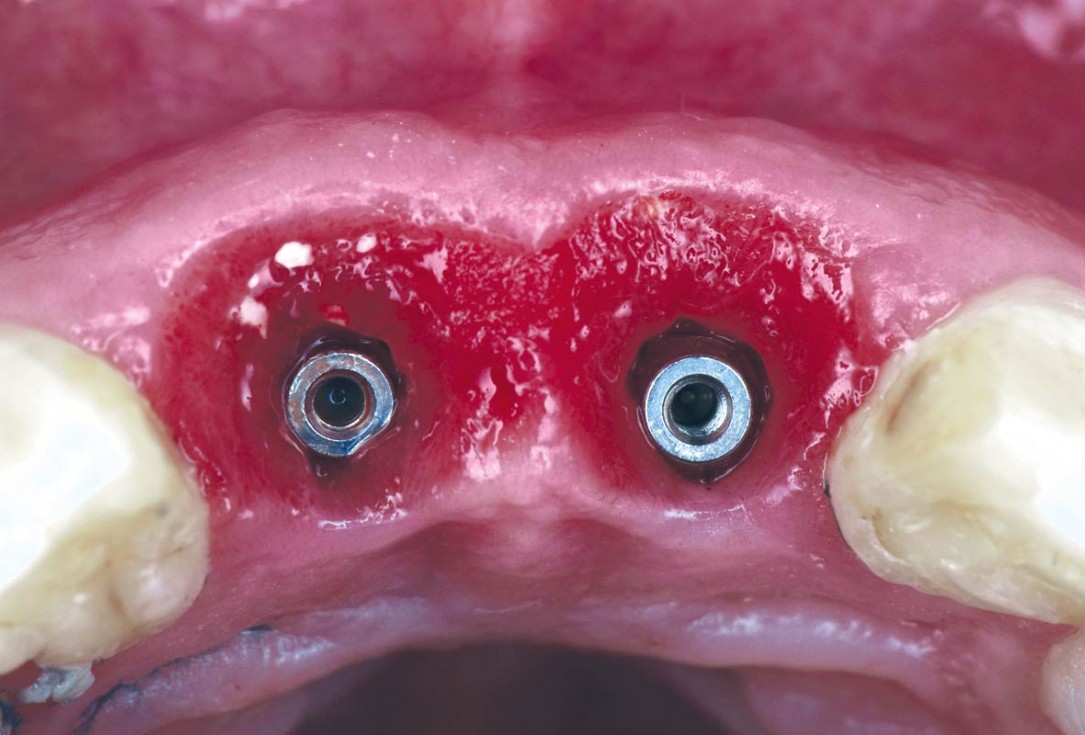

04/22 - Immediate implants are placed after extractioncerabone® and mucoderm® for immediate implantation in the aesthetic area - Dr. D. Robles

05/22 - Immediate implants are placed after extraction and the gap is filled with cerabone®cerabone® and mucoderm® for immediate implantation in the aesthetic area - Dr. D. Robles